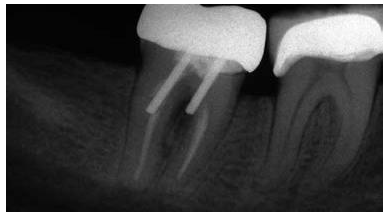

在根尖片上,根管內(nèi)牙膠的最短長度應(yīng)當(dāng)是5mm以確保充足嚴(yán)密的根尖封閉。

牙髓治療后的牙齒經(jīng)過樁道的預(yù)備,根尖部的牙膠是抵抗根尖周區(qū)域細(xì)菌傳播的屏障。許多研究結(jié)果都已經(jīng)證實(shí)當(dāng)根尖部的牙膠長度僅僅是2mm到3mm時(shí),根管內(nèi)存在嚴(yán)重的滲漏;根尖部牙膠量為4mm到5mm能保證充足的根尖封閉。盡管多數(shù)研究結(jié)果都表明4mm的根尖牙膠量能提供充足的根尖封閉,但是樁道預(yù)備時(shí)要精確地達(dá)到4mm是非常困難的,根尖片拍攝角度的差異可能會導(dǎo)致根尖部保留的牙膠少于4mm。因此在根尖片上,根尖部牙膠5mm比4mm更為對根尖封閉安全有效。

除了磨牙之外,所有牙齒理想的樁長度是由保存根尖部5mm牙膠封閉來決定的,同時(shí)將樁與牙膠嚴(yán)密接觸。對于磨牙而言,僅僅是首選根管應(yīng)當(dāng)被使用,同時(shí)樁進(jìn)入根管內(nèi)的長度不能超過7mm。應(yīng)當(dāng)避免使用短樁。

因此,長度為牙根長3/4的樁能夠提供最強(qiáng)的剛性,同時(shí)保證產(chǎn)生最小程度的牙根偏轉(zhuǎn)。盡管如此,對于多數(shù)牙齒而言,按照此表面的理想樁長度原則進(jìn)行操作是非常困難的。當(dāng)一顆牙齒具有牙根平均長度或者短于平均長度的牙根時(shí),同時(shí)修復(fù)的樁長度占據(jù)牙根長度的2/3或者更長,在此情況下,就不能保存5mm的根尖牙膠封閉。因此,理想的樁長度是由保存根尖部5mm牙膠封閉來決定的,同時(shí)將樁與牙膠嚴(yán)密接觸。